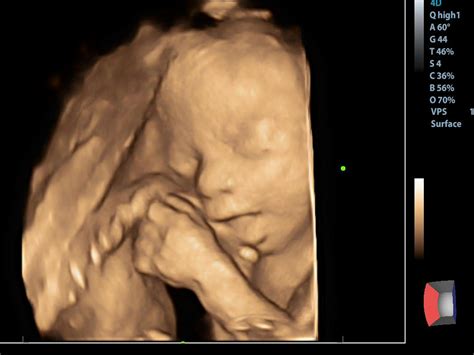

Rolul Ecografiei 3D/4D în Trimestrul 3

Ecografia 3D și 4D reprezintă tehnologii avansate de imagistică utilizate în timpul sarcinii pentru a oferi imagini detaliate ale fătului. Ecografia 3D utilizează ultrasunetele pentru a crea imagini tridimensionale ale fătului, oferind o imagine mai clară a structurilor anatomice fetale. Ecografia 4D este o formă avansată de ecografie 3D, care adaugă elementul de timp, oferind imagini în mișcare în timp real, creând practic un video al fătului în mișcare, permițând observarea expresiilor faciale și a activităților fetale în direct.

Comparativ cu ecografia clasică, 2D, cele două variante mai performante au avantajul că oferă imagini mai clare și mai detaliate ale fătului. Astfel, aceste forme de ecografie devin extrem de utile pentru a oferi viitorilor părinți o imagine a ce înseamnă malformația fetală descoperită și evoluția acesteia. Este important de menționat că imaginile detaliate furnizate de ecografiile 3D/4D pot ajuta medicii să planifice intervenții medicale prenatale sau postnatale necesare. Acestea oferă o înțelegere mai bună a problemelor medicale, astfel că simplifică procesul de diagnostic. În plus, prin intermediul ecografiei 3D sau 4D, conexiunea dintre părinți și făt se consolidează.